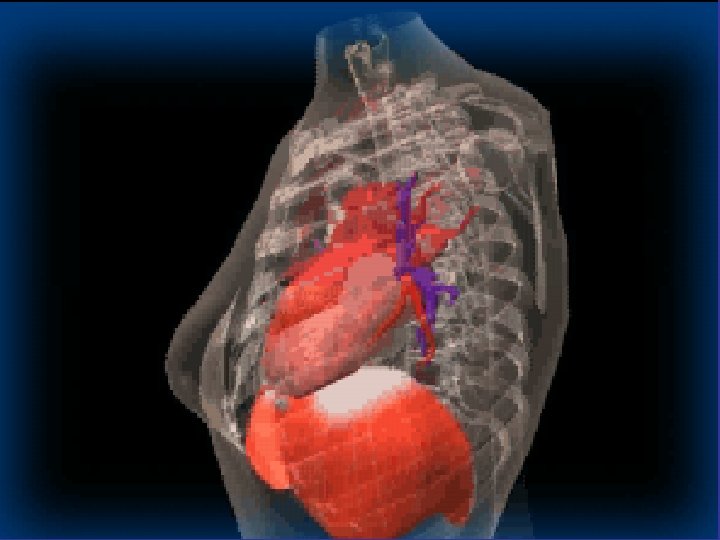

Lobes and Fissures